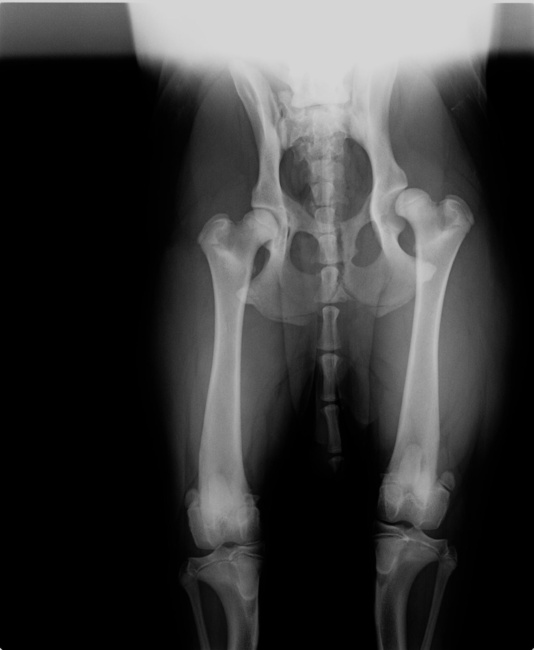

Ik zet even als je het goed vind (geef anders even een PB-tje dan haal ik hem weg) je röntgen foto uit je profiel hierbij, zodat andere het ook makkelijker kunnen zien en misschien je verder mee kunnen helpen.

(foto van Gunther's profiel)

ben ik nou blind? die andere heup is toch ook niet goed? ze vallen beiden niet in de heupkommen. het lijken de heupen van cash wel, en dat voor zo'n jonge hond

een hd a foto.... de foto boven daar ligt de hond niet echt recht.

dat hij niet recht ligt klopt, ik hoop dan ook dat ze betere foto's hebben om hun diagnose mee te staven.